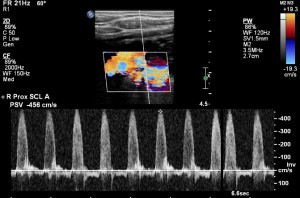

First, check the blood pressure in both arms. If it is equal, that points against significant narrowing. Next, you will need to images the subclavian artery. An ultrasound should be a first step. On ultrasound, elevated flow velocities and turbulent flow are the markers of significant subclavian artery stenosis: